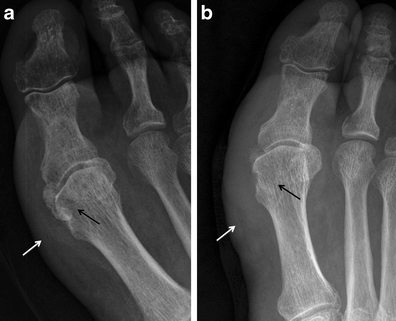

Hallucal sesamoid fracture. Oblique (a) and AP (b) radiographs at the forefoot in a patient after deceleration injury. There are dorsal dislocations of the first and second metatarsophalangeal joints (black arrows), with a comminuted fracture of the lateral hallucal sesamoid (white arrows). Note that the sesamoid fracture pieces would fit together perfectly. The medial hallucal sesamoid is also fractured in this patient